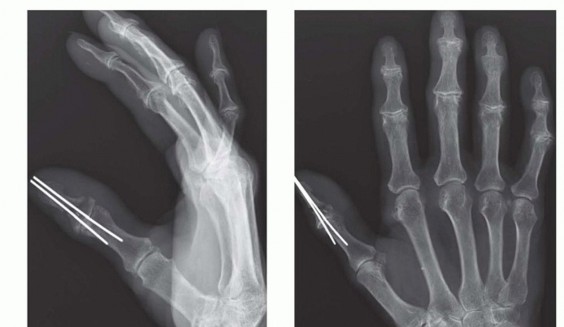

When the patient arrives in the emergency department, standard radiographs of the amputated parts and the injured limb are obtained (FIG 4).Laboratory evaluations should include a complete blood count, basic metabolic panel, coagulation panel, drug screen, and blood type and crossmatch. Other preoperative tests are ordered as indicated by the patient's age and comorbidities.

FIG 4 • A. Standard posteroanterior (PA) radiograph of the injured hand. B. A radiograph of the amputated parts is also obtained by placing the bag containing the parts directly on the x-ray cassette.